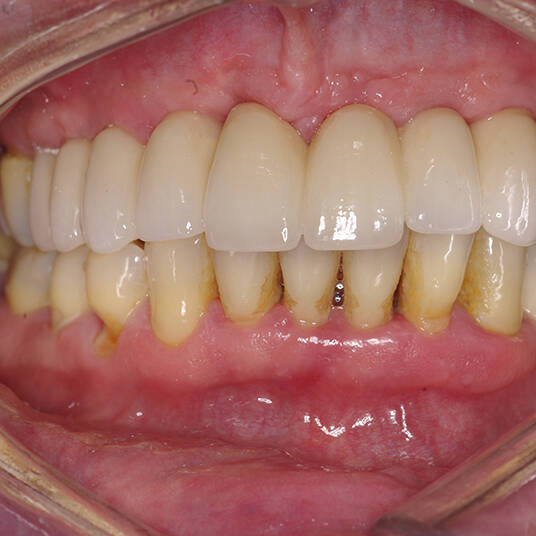

Na Clínica Pontes Odontologia, somos referência em implantes dentários em Fortaleza, oferecendo tratamentos de alta qualidade e tecnologia de ponta. Os implantes dentários são estruturas de titânio posicionadas cirurgicamente no osso maxilar ou mandibular para substituir as raízes dos dentes ausentes. Essa técnica permite a fixação de próteses personalizadas, restaurando a função mastigatória, a estética e a autoestima dos nossos pacientes.

Utilizamos a tecnologia CAD CAM, um sistema avançado que possibilita a confecção precisa das próteses dentárias diretamente sobre os implantes. Esse método inovador garante um ajuste perfeito, um resultado estético superior e proporciona muito mais conforto e durabilidade. Com o CAD CAM, nossos pacientes contam com um processo mais rápido e previsível para alcançar o sorriso desejado.